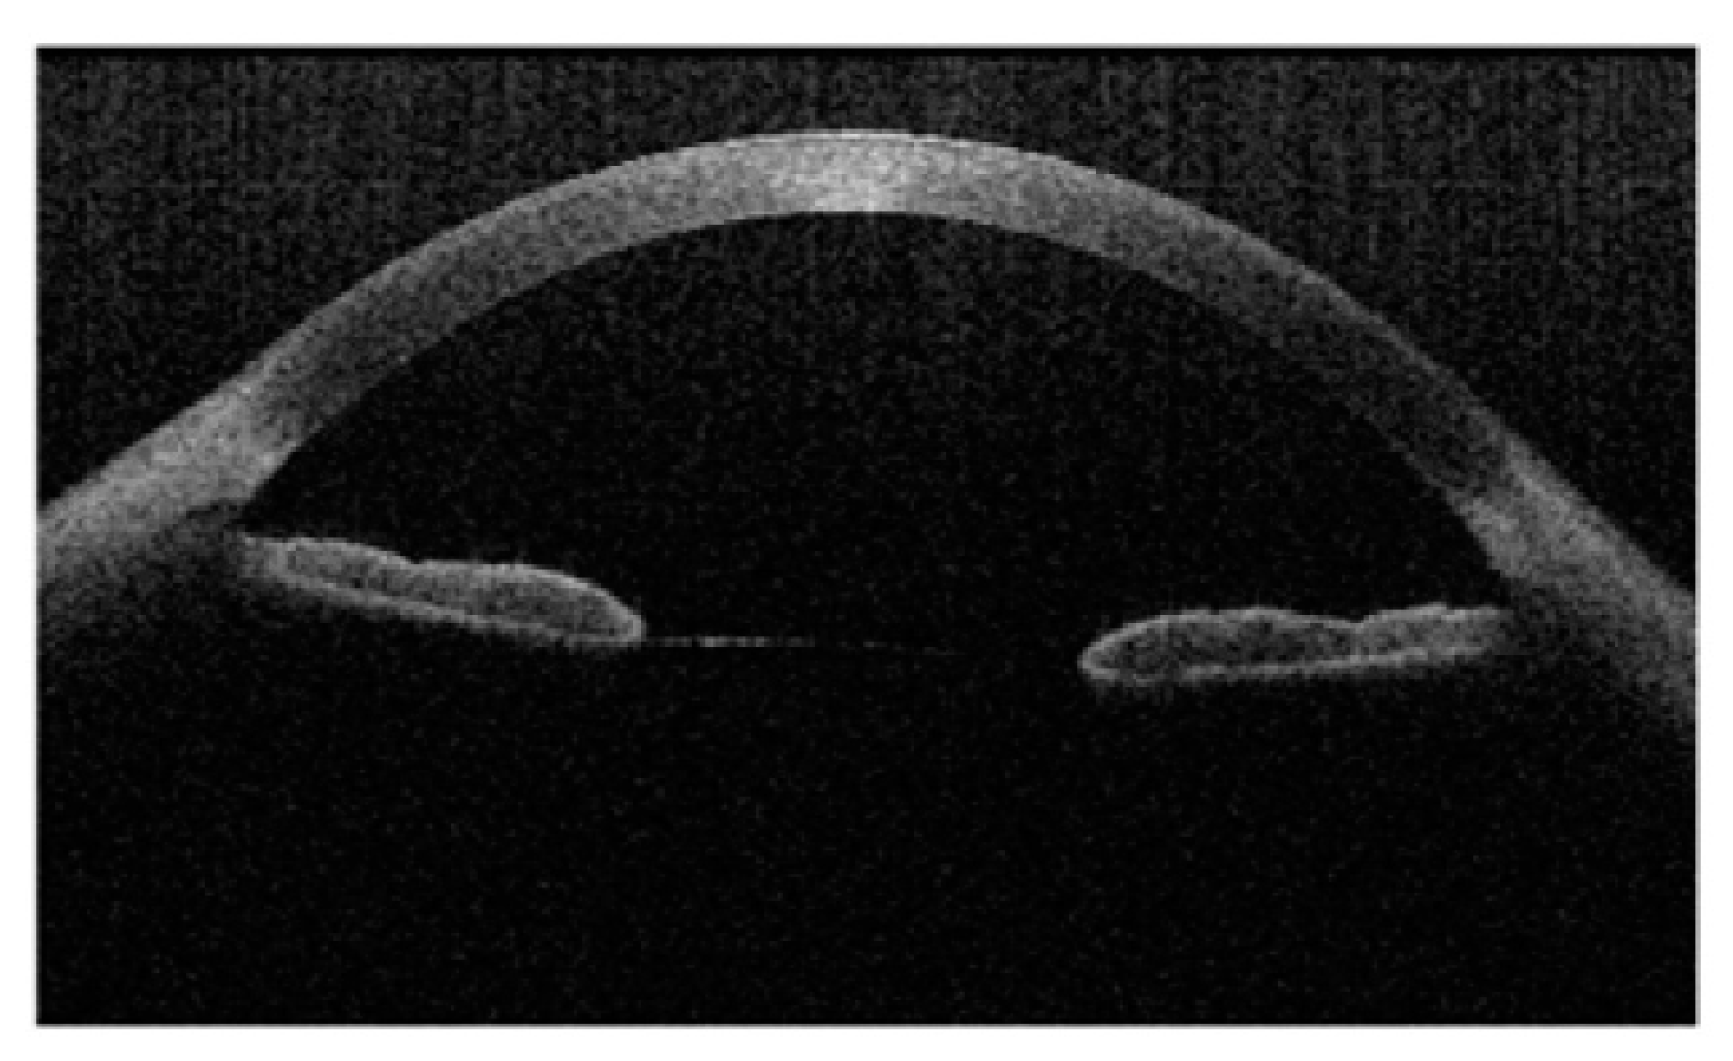

3.3. Anterior Segment Optical Coherence Tomography (AS-OCT)

3.4. Topography, Tomography, and Wavefront Imaging in Space